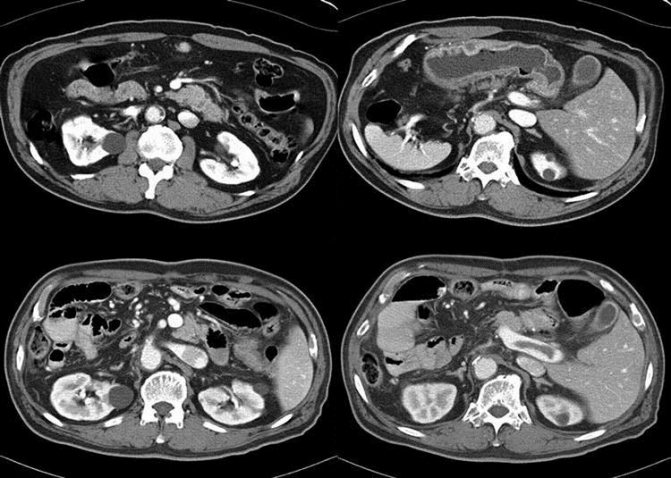

Хронические болезни почек на УЗИ

С помощью УЗИ диагностируют и наблюдают пациентов с хроническими заболеваниями почек. При гломерулосклерозе, атрофии канальцев, интерстициальном воспаление или фиброзе на УЗИ корковый слой почек гиперэхогенный, кортикомедуллярная дифференцировка сглажена. При прогрессировании болезни паренхима истончается и уменьшается размер почек.

Рисунок. На УЗИ хронический пиелонефрит (1): почка уменьшена до 74 мм, контур неровный за счет локального уменьшения толщины коркового слоя. На УЗИ хронический гломерулонефрит (2): размер почки 90 мм, кортикомедуллярная дифференцировка паренхимы сглажена, тонкий корковый слой повышенной эхогенности. На УЗИ нефротический синдром (2): гиперэхогенная почка без четкой дифференциации на корковое и мозговое вещество.

Рисунок. На УЗИ пациент с ХПН (1, 2, 3): почки уменьшены в размерах до 70х40 мм, толщина паренхимы 7 мм, кортикомедуллярная дифференцировка сглажена. На УЗИ терминальная стадия ХПН: почка очень маленькая — 36 мм, эхогенность значительно повышенна, различить паренхиму и синус не представляется возможным.